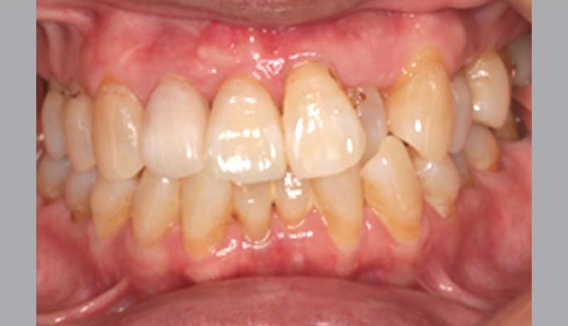

症例紹介

歯周病で多くの歯を失ってしまった方や、

歯周病が原因で抜歯を勧められている方、

歯周病の専門家に相談してみたいという方も、

ぜひ当院にお任せください。